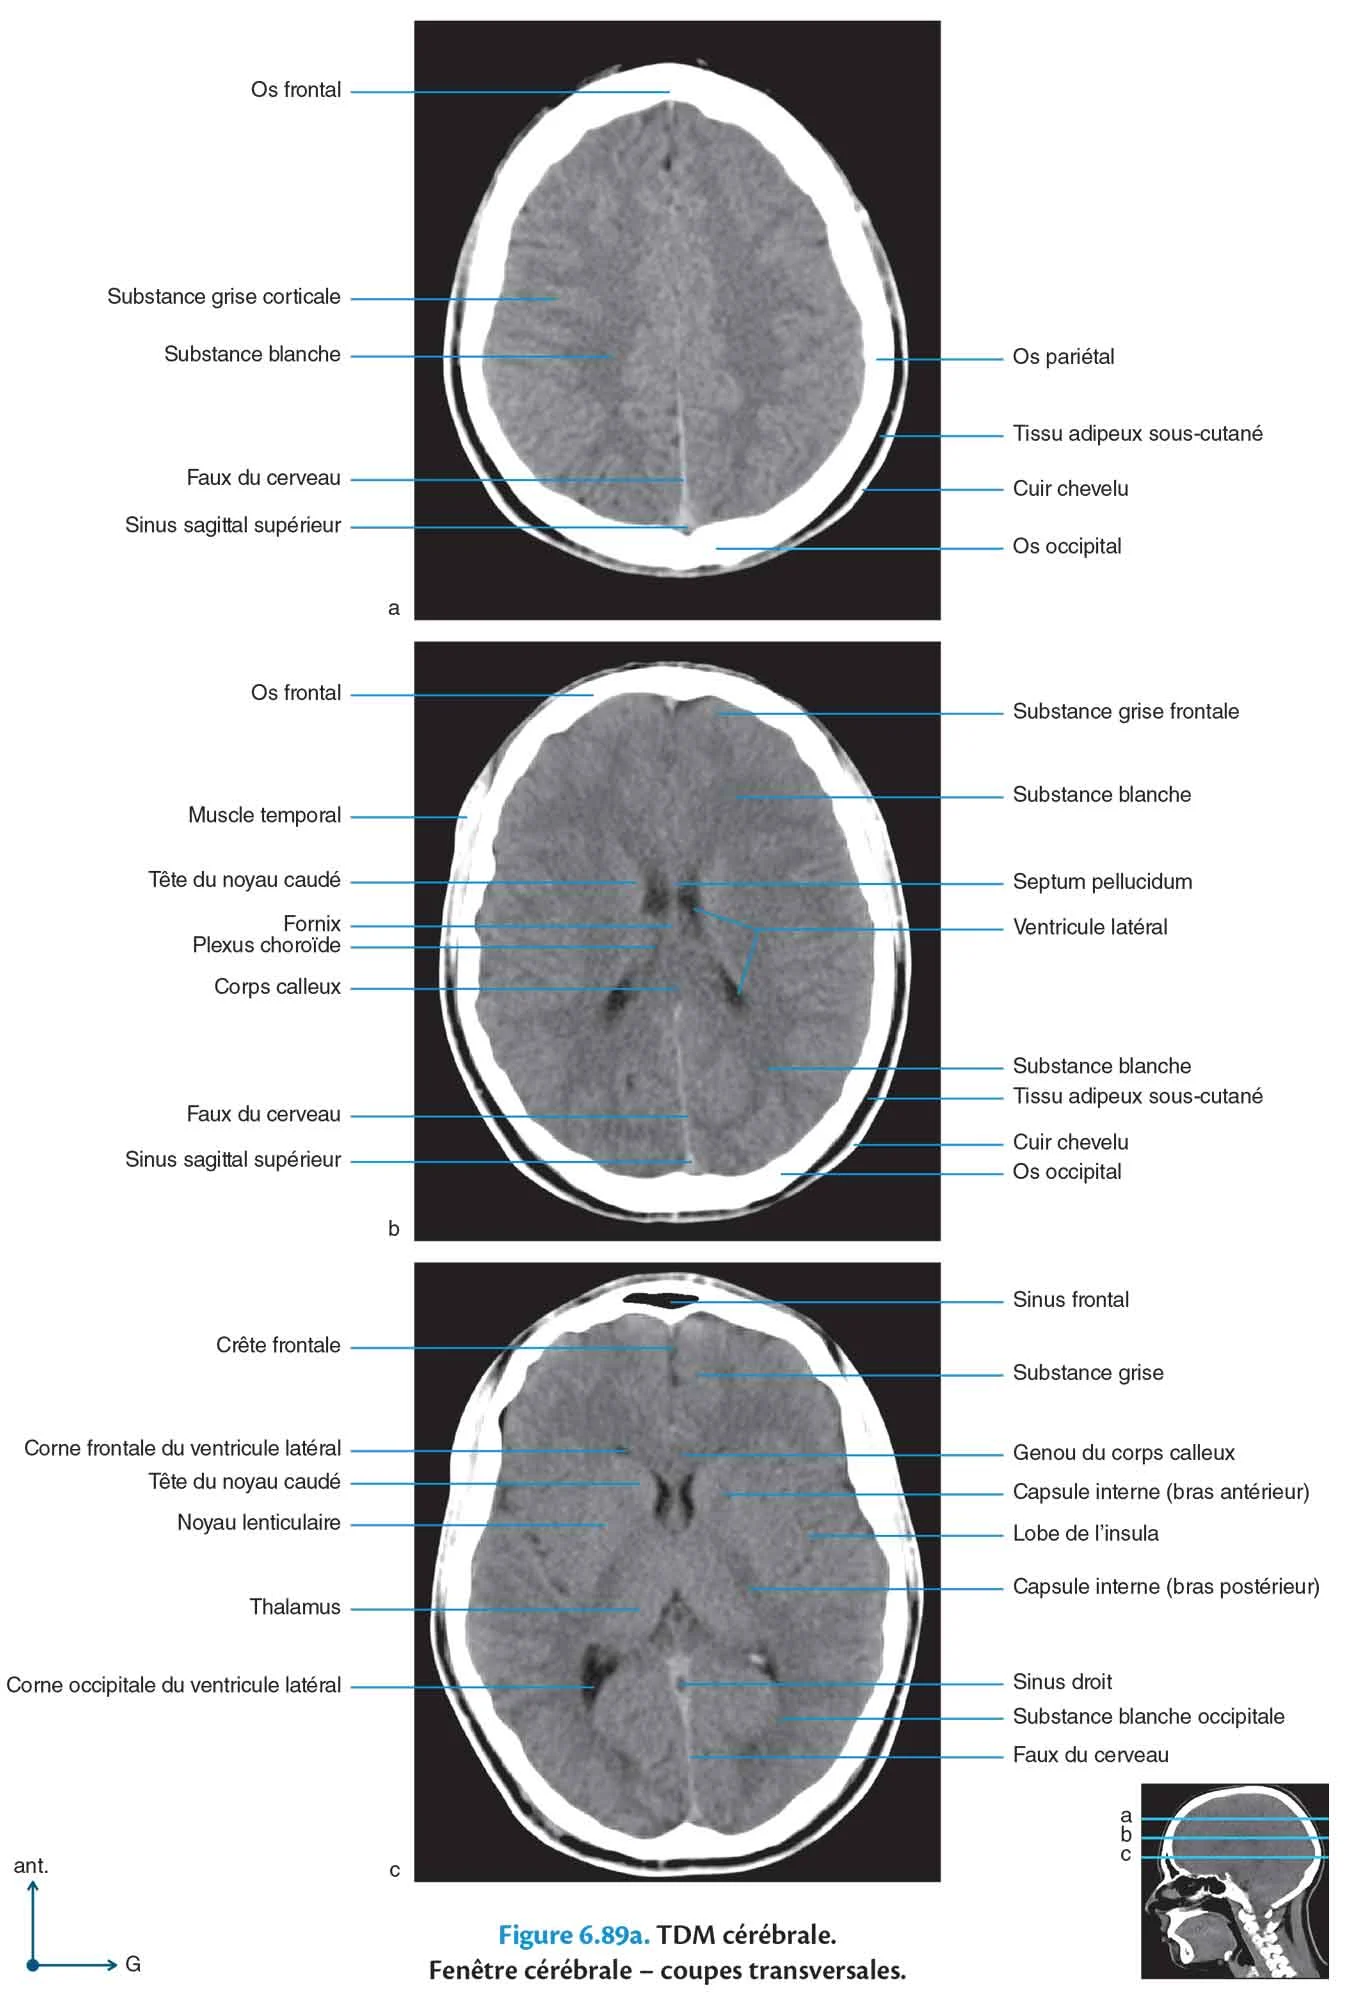

TDM cérébrale

Fig 6.89a